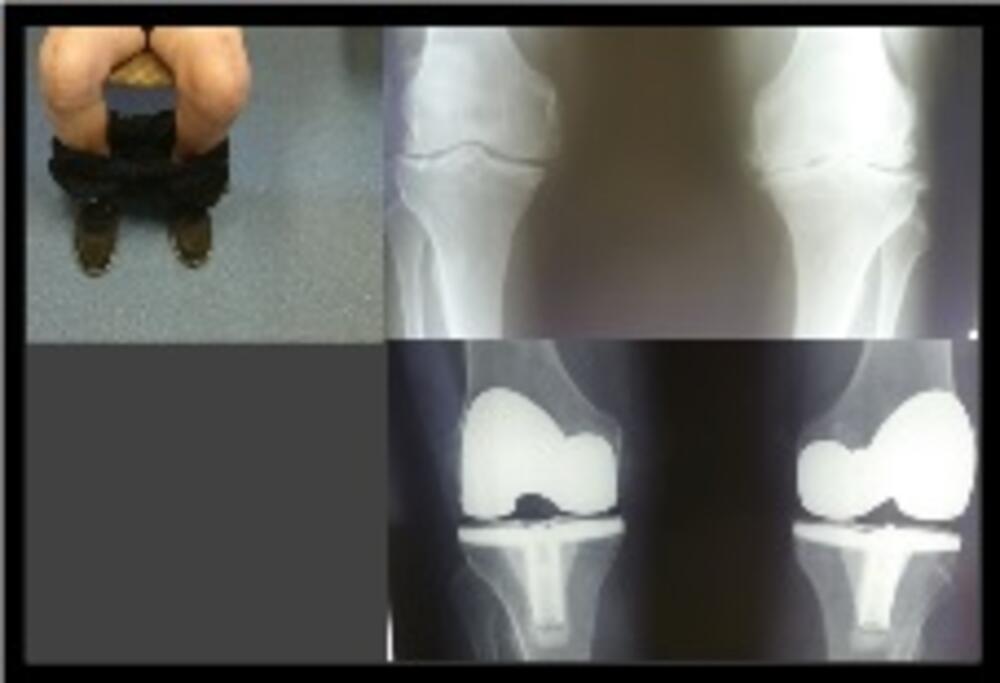

Obostrana gonartroza je čest nalaz. Pacijenti sa obostranom gonartrozom mogu da budu operisani obostranom artroplastikom – zamjenom koljena u jednom aktu, tokom jedne hospitalizacije ili mogu najprije da operišu jedno, pa nakon određenog vremena i drugo koljeno.